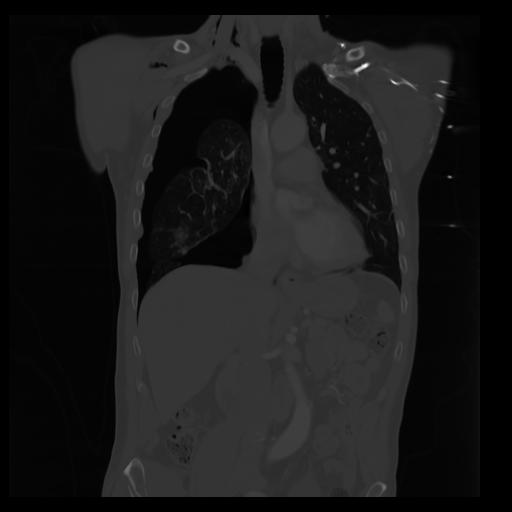

29 CUERPO,CE,Coronal,3.000,CUERPO,Coronal,